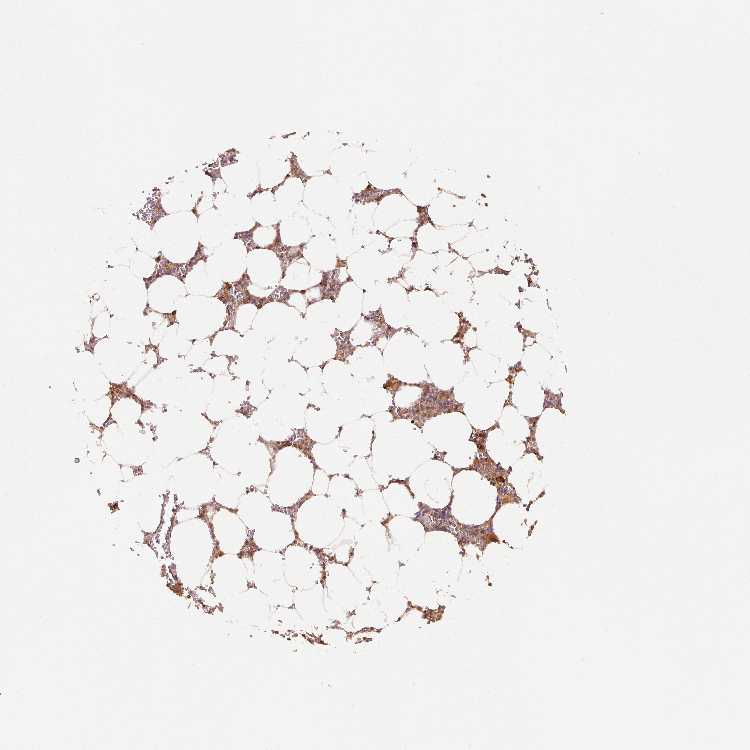

BONE MARROW - Antibody stainingi

Antibody staining in the annotated cell types in the current human tissue is reported as not detected, low, medium, or high, based on conventional immunohistochemistry profiling in selected tissues. This score is based on the combination of the staining intensity and fraction of stained cells.

Each image is clickable and will lead to virtual microscopy that enables deeper exploration of all samples and also displays staining intensity scores, fraction scores and subcellular localization as well as patient and tissue information for each sample.

Antibody HPA048983Antibody CAB017562

Hematopoietic cells MediumHigh